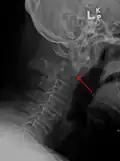

Repair of a dens fracture

A fracture of both pedicles of the axis is termed a Hangman's fracture.

Fractures of the dens are classified into three categories according to the Anderson Alonso system:

• Type I fracture - Extends through the tip of the dens. This type is usually stable.

• Type II fracture - Extends through the base of the dens. It is the most commonly encountered fracture for this region of the axis. This type is unstable and has a high rate of non-union.

• Type III fracture - Extends through the vertebral body of the axis. This type can be stable or unstable and may require surgery.[1]